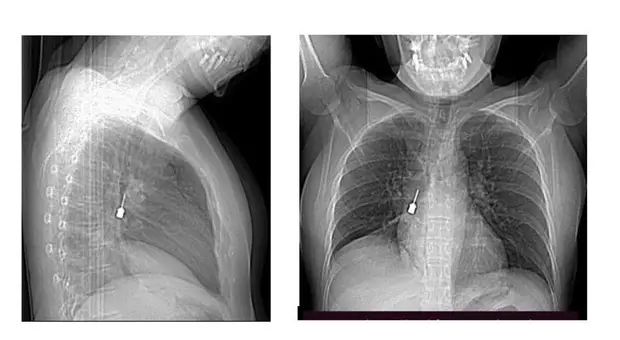

Tosse e dolore al petto, i medici scoprono un cacciavite odontoiatrico nel bronco di una donna: l'operazione salva-vita

Un cacciavite odontoiatrico inalato accidentalmente e rimasto incastrato in un bronco polmonare. È la scoperta choc che ha portato una giovane donna al Pronto Soccorso dopo giorni di tosse...